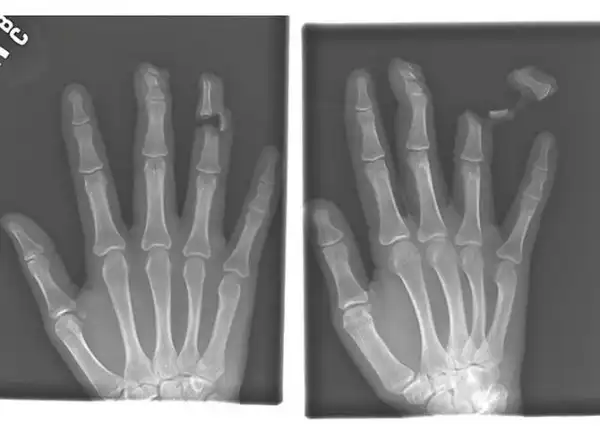

Гвоздь в костях указательного и среднего пальцев взрослого мужчины.